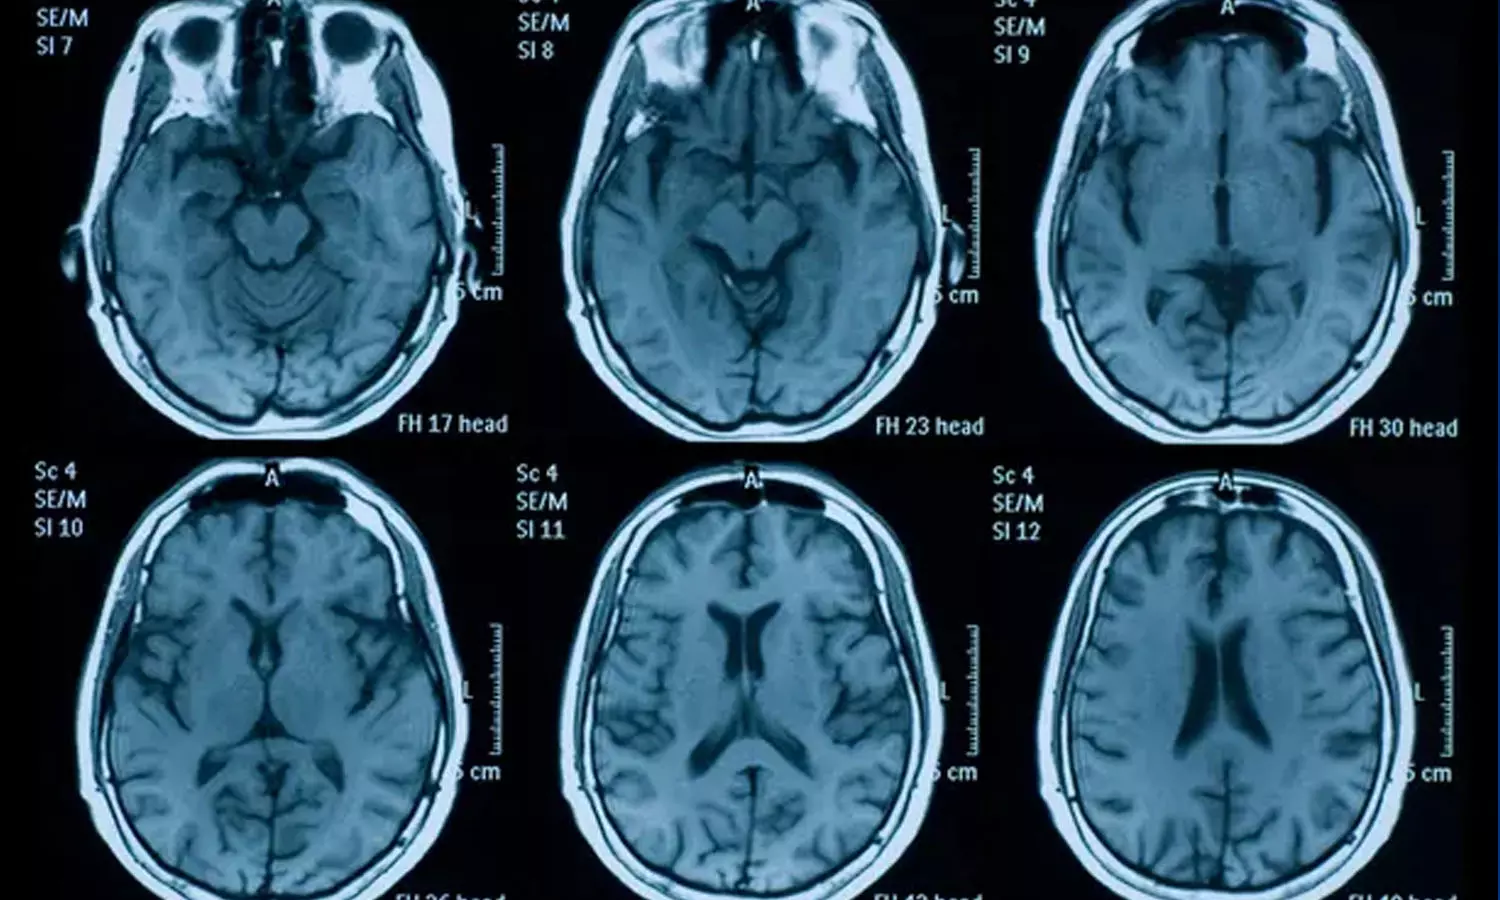

പഠനത്തിന്റെ ഭാഗമായി ന്യൂറോ സയന്റിസ്റ്റായ ഗ്വെനെല്ലെ ഡൗഡും സഹപ്രവർത്തകരും കോവിഡിനു മുൻപ് ശേഖരിച്ച 785 പേരുടെ തലച്ചോറുകൾ എംആർഐ സ്കാനിങ് ഉപയോഗിച്ച് പരിശോധിച്ചു. 38 മാസങ്ങൾക്കു ശേഷം ഇതിൽ 401 പേർക്ക് കൊവിഡ് ബാധിച്ചിരുന്നു. തുടർന്ന് ആദ്യ സർവേയിൽ പങ്കെടുത്ത മുഴുവൻ പേരെയും വീണ്ടും എംആർഐ സ്കാനിങിനു വിധേയമാക്കി.

തലച്ചോറിലെ ഗ്രേ മാറ്ററിൽ സാധാരണ വാർധക്യത്തിന്റെ ഭാഗമായി 0.2 ശതമാനം മാത്രമാണ് മാറ്റമുണ്ടാകുക. രണ്ടാമത്തെ സ്കാനിന് ശരാശരി 4.5 മാസം മുമ്പ് രോഗം ബാധിച്ചവരിൽ, ഓർബിറ്റോഫ്രോണ്ടൽ കോർട്ടെക്സ്, പാരാഹിപ്പോകാമ്പൽ ഗൈറസ് എന്നറിയപ്പെടുന്ന ഗന്ധവുമായി ബന്ധപ്പെട്ട തലച്ചോറിന്റെ ഭാഗങ്ങളിൽ ചാരനിറത്തിലുള്ള ദ്രവ്യത്തിന്റെ കനം ഗണ്യമായി കുറയുന്നതായി ഗവേഷകർ കണ്ടെത്തി.

SARS-CoV-2 അണുബാധയുള്ളവർക്ക് പോലും തലച്ചോറിൽ ചില മാറ്റങ്ങൾ ഉണ്ടാവാമെന്ന് ഗവേഷകർ പറയുന്നു. എന്നാൽ തലച്ചോറിന്റെ വലുപ്പത്തിലുണ്ടായത് ചെറിയ മാറ്റങ്ങൾ മാത്രമാണെന്നും ഇത് നഗ്നനേത്രങ്ങൾ കൊണ്ട് തിരിച്ചറിയാൻ കഴിയില്ലെന്നും ഗവേഷകർ വ്യക്തമാക്കി.